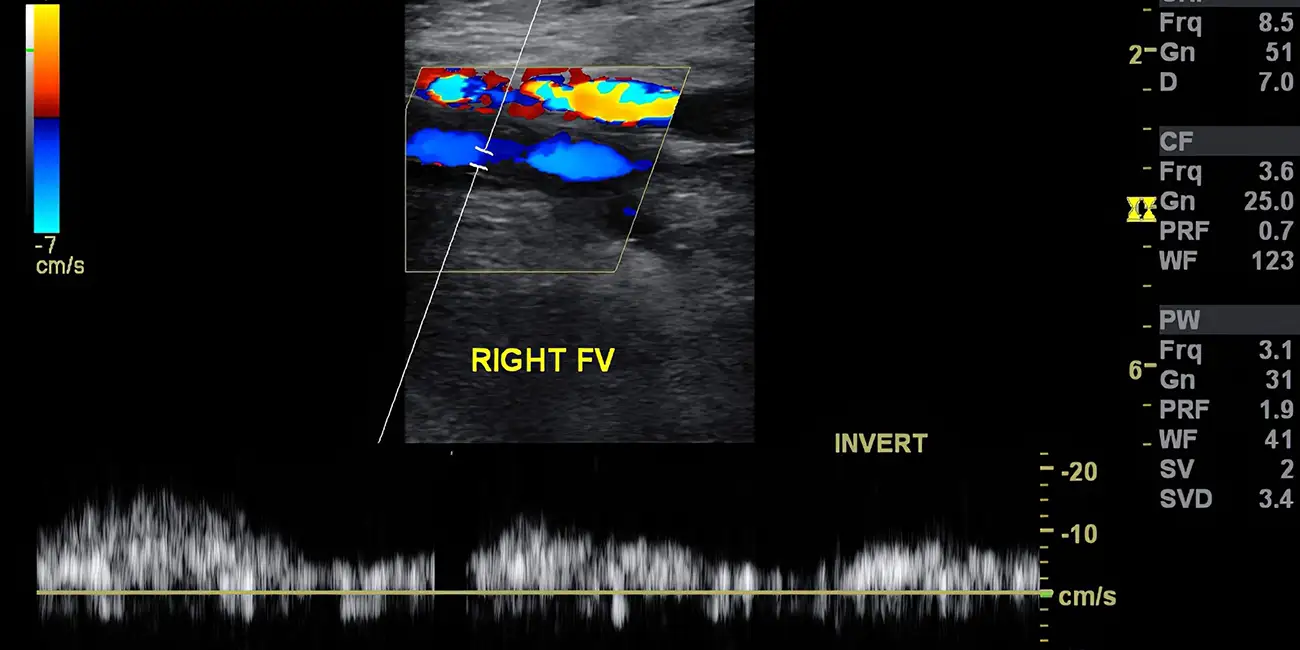

Permite visualizar el flujo sanguíneo en tiempo real, ayudando a identificar bloqueos, estrechamientos, coágulos o malformaciones en las venas y arterias. Es crucial para diagnosticar afecciones como la trombosis venosa profunda, la insuficiencia venosa crónica y los aneurismas.

Se utiliza para evaluar la enfermedad arterial periférica (EAP), permitiendo ver las áreas donde las arterias están estrechadas u obstruídas y así medir la velocidad del flujo sanguíneo.